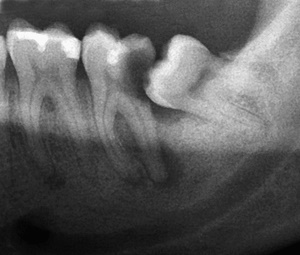

우리가 사랑니라고 부르는 것은 큰 어금니 중 세 번째 위치에서 제일 마지막에 나오는 치아입니다. 사랑니가 나올 때에는 첫사랑을 하듯이 아프다고 하여 붙여진 이름이라고 하는데요. 다른 이름으로는 ‘지치’라고 합니다. 지치는 사리를 분별할 수 있는 지혜가 생긴다는 뜻입니다.

사랑니는 보통 큰 어금니와 비슷하게 생겼습니다. 사랑니의 형태나 크기는 매우 다양하다고 하는데요. 보통의 어금니 보다 깊이 나기 때문에 빼기 어렵거나 절개를 통해 힘들게 빼야 하는 경우가 많습니다. 원래 사랑니는 음식물을 갈아 내기 위한 용도라고 하는데요. 이것은 치아의 퇴화 현상이라고 생각하시는 분들도 많이 계십니다.